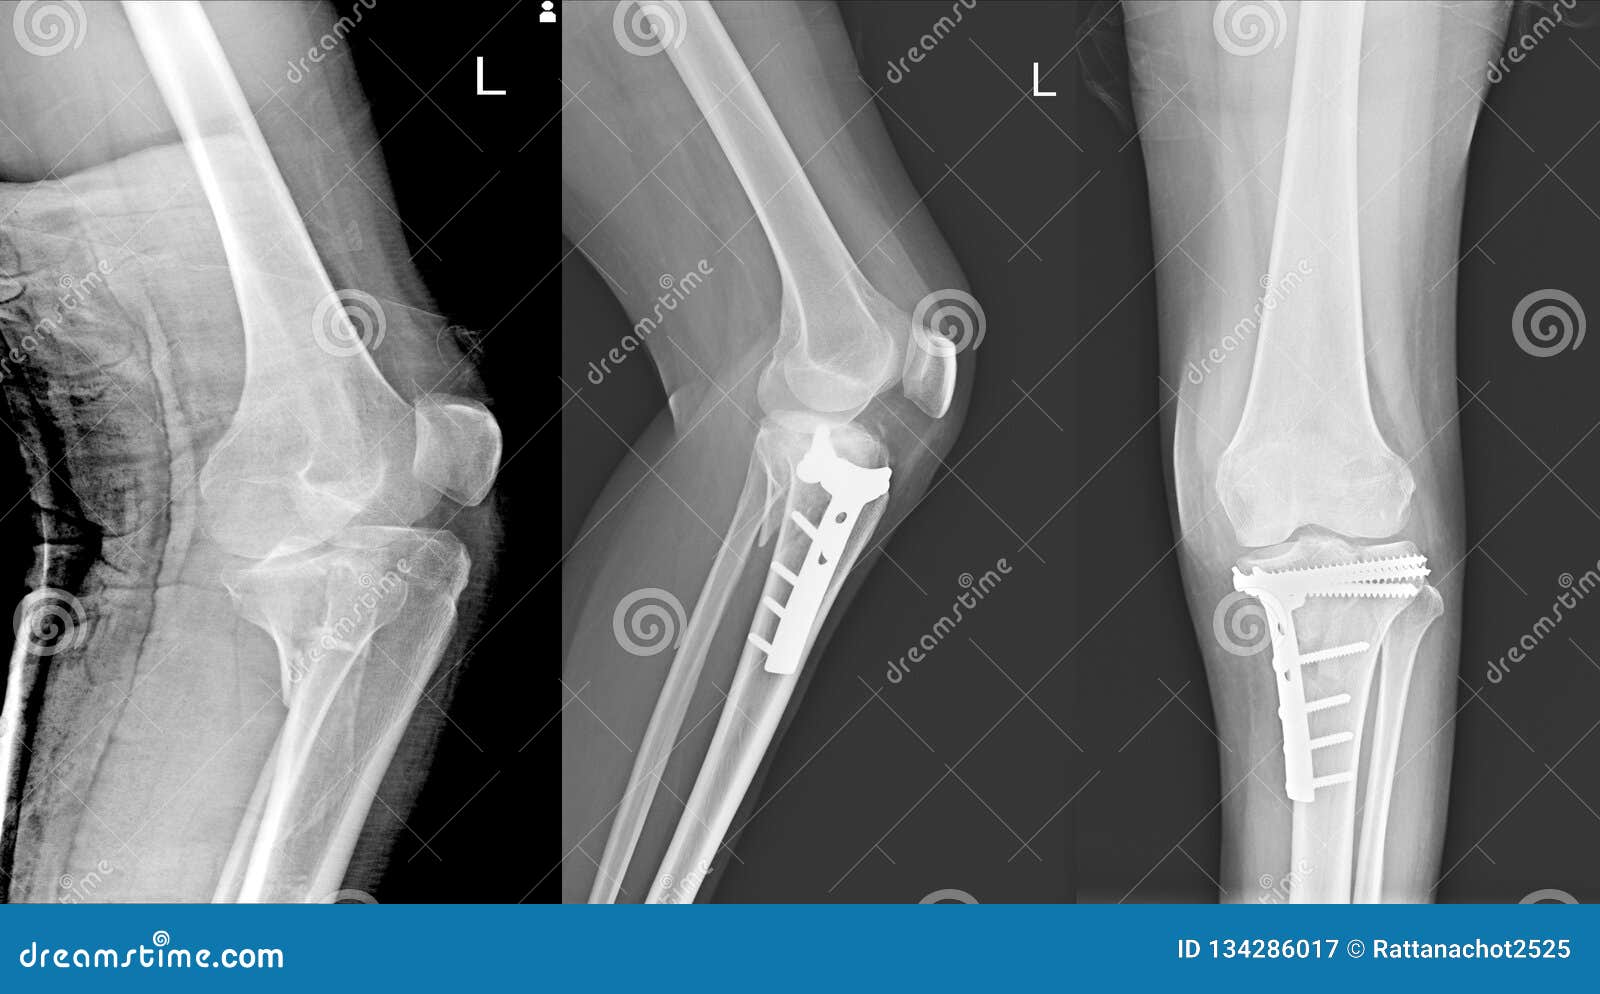

Как и при любой травме коленного сустава для постановки правильного диагноза выполняется рентгенография, на которой-то и можно увидеть перелом. Обычно рентгенографию выполняют в прямой и боковой проекциях, а для диагностики вертикальных переломов выполняют еще и осевую (аксиальную, или Merchant) проекцию.

Прямая (слева) и боковая (справа) проекции, на которых виден горизонтальный перелом надколенника со смещением отломков. Осевая проекция. Вертикальный перелом. Обратите внимание на возникшую в результате смещения ступеньку на скользящей поверхности надколенника.

Осевая проекция. Вертикальный перелом. Обратите внимание на возникшую в результате смещения ступеньку на скользящей поверхности надколенника.Иногда для более точного диагноза могут потребоваться компьютерная и/или магнитно-резонансная томография, но, в подавляющем большинстве случаев, достаточно рентгенографии.

На рентгенограмме показан перелом тела надколенника без смещения.

На рентгенограмме продемонстрирован перелом нижнего полюса надколенника.

Перелом надколенника слева со смещением отломков. Необходима операция.

Краевой перелом надколенника, хорошо видимый на аксиальной рентгенограмме.

Рентгенограммы после остеосинтеза надколенника по Веберу.